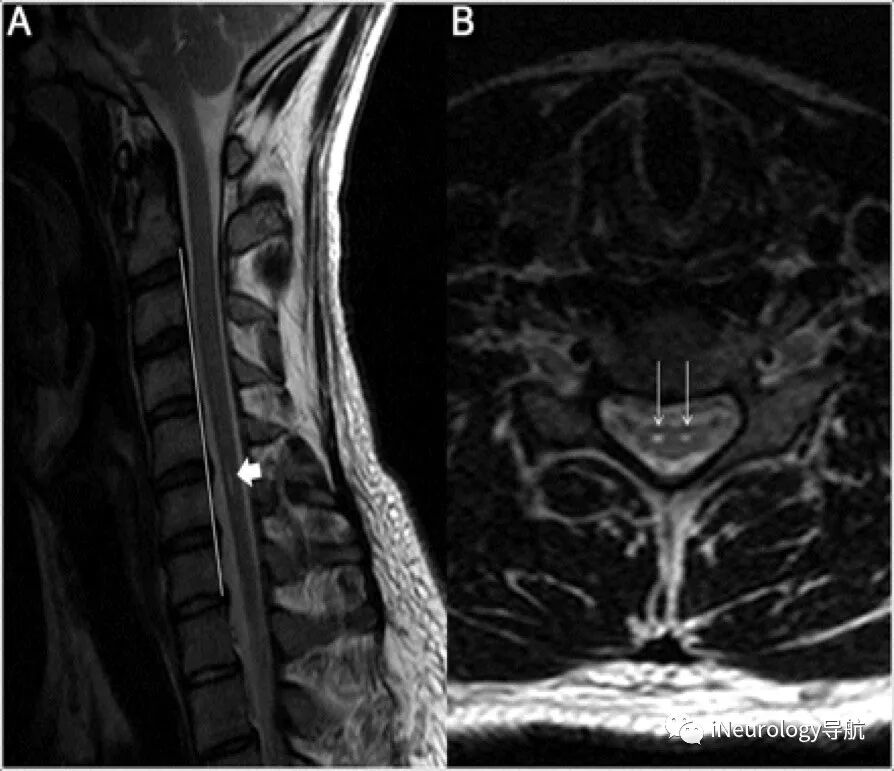

Tips003 C2分離症 脊髄障害のメカニズムは 亀田メディカルセンター 亀田総合病院 脊椎脊髄外科 医療関係者向け

平山病 一种良性自限性的临床疾病 腾讯新闻

Neurology病例 平山病的前角细胞高信号 Ineurology导航 微信公众号文章阅读 Wemp